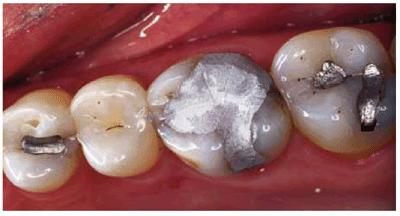

Sequence for Premolars

The type of foundation restoration for a premolar is determined by the amount

of available tooth structure. This requires making an estimation of the amount

of tooth structure that will remain after the crown preparation. If there is a

moderate amount of tooth structure, the tooth can be restored like a molar

using amalgam or composite as the core material. Similar to a molar, the

retention for the core would be gained by either mechanical retention and/or

dentin bonding. If there is minimal tooth structure, it is best to use the same

treatment sequence as described for an anterior tooth. First, the tooth is

prepared for the indicated crown. Then the amount of remaining tooth structure

is evaluated. If the premolar has two roots, prefabricated posts can be

cemented in the two canals (Figur 323s1823d es 18-18A, and 18-18B). It is usually not possible or

even necessary to make these posts very long because of canal curvature.

However, because the canals are usually not parallel, following placement of

the core, the posts and core are virtually impossible to dislodge. For a small

premolar, composite resin is a better core material than amalgam because the

prefabricated posts weaken the amalgam. If there is minimal or no coronal tooth

structure, a cast post should be considered, especially for a single rooted

premolar.

Figur 323s1823d e 18-18A: Prefabricated post for additional core retention.

Figur 323s1823d e 18-18B: Prefabricated posts in the two canals of a premolar prior to core placement. It is usually not possible to make these posts very long because of canal curvature. Because canals are usually not parallel to each other, the core is well retained by posts.